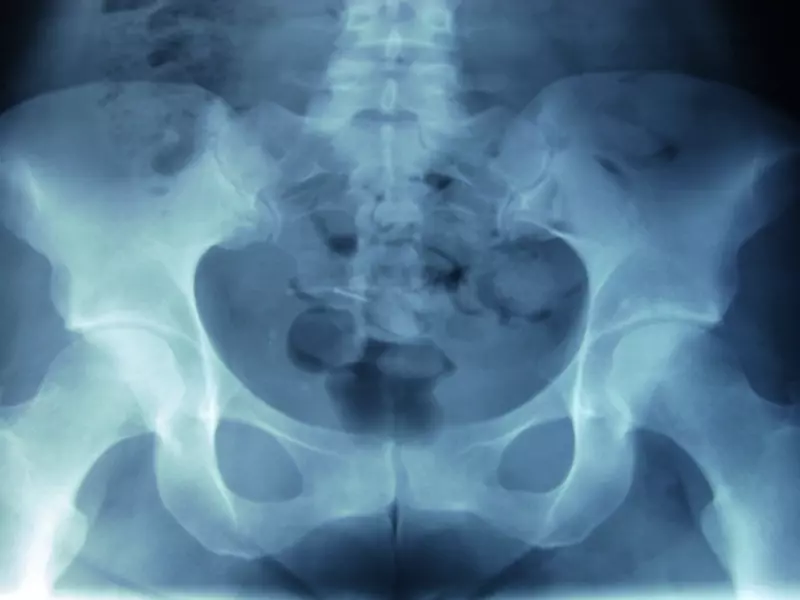

• W jakim celu wykonuje się kontrolne badania RTG po leczeniu złamań stopy i jakie mogą być ich wyniki.

Wstępna diagnoza urazów powinna być oparta na wnikliwej ocenie klinicznej obejmującej także badanie radiologiczne. Złamania palców stopy występują zwykle po urazach bezpośrednich, np. poprzez uderzenie lub zmiażdżenie. Objawami są bardzo silny ból lub ból pojawiający się w trakcie chodzenia, opuchlizna, obrzęk, pęknięte naczynia krwionośne (w postaci siniaka), zasinienie złamanego palca bądź nawet deformacja uszkodzonego palca. Często w celu odróżnienia złamania palca u stopy od zwichnięcia wykonuje się próbę delikatnego poruszenia palcem. Jeżeli słyszalne jest tarcie lub „trzeszczenie”, oznacza to, że palec jest prawdopodobnie złamany. Dodatkowo może pojawić się uczucie osłabienia. W zależności od samego mechanizmu, który spowodował uraz i powikłania, stosuje się odmienne postępowanie lecznicze. W przypadku złamań bez przemieszczenia wykonuje się zabiegi fizjoterapeutyczne, głównie z zakresu fizykot...